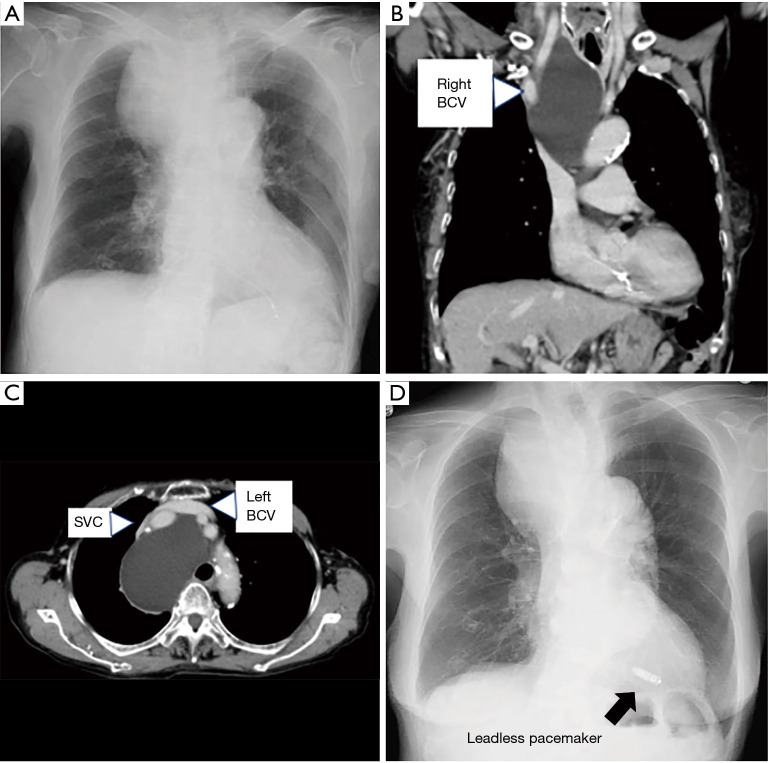

Cardiovascular implantable electronic devices (CIEDs) such as pacemakers and implantable cardioverter defibrillators require the placement of a transvenous lead through the superior vena cava (SVC), which can be difficult if there is stenosis or obstruction of the SVC. Moreover, SVC syndrome may occur after the lead is inserted even if the SVC was intact before the implantation. Therefore, there is need of an appropriate strategy for handling stenosis or obstruction of SVC during lead placement. In addition, advances are being made in CIEDs that do not require transvenous leads, and thus CIEDs without a transvenous lead should be considered depending on the indications and urgency of the particular case. This manuscript is divided into (I) device therapy for patients with SVC obstruction and (II) therapeutic strategy for SVC obstruction after lead implantation. In patients with SVC syndrome, treatment of the SVC occlusion should be based on the individual pathophysiology, and depending on the indications and urgency of the case, treatment with CIEDs that do not require transvenous leads should be considered. Further data must be accumulated to clarify the long-term prognosis of device implantation after treatment of SVC occlusion. In addition, transvenous lead extraction is now widely used for device-related SVC obstruction, and this procedure also merits further accumulation of data.